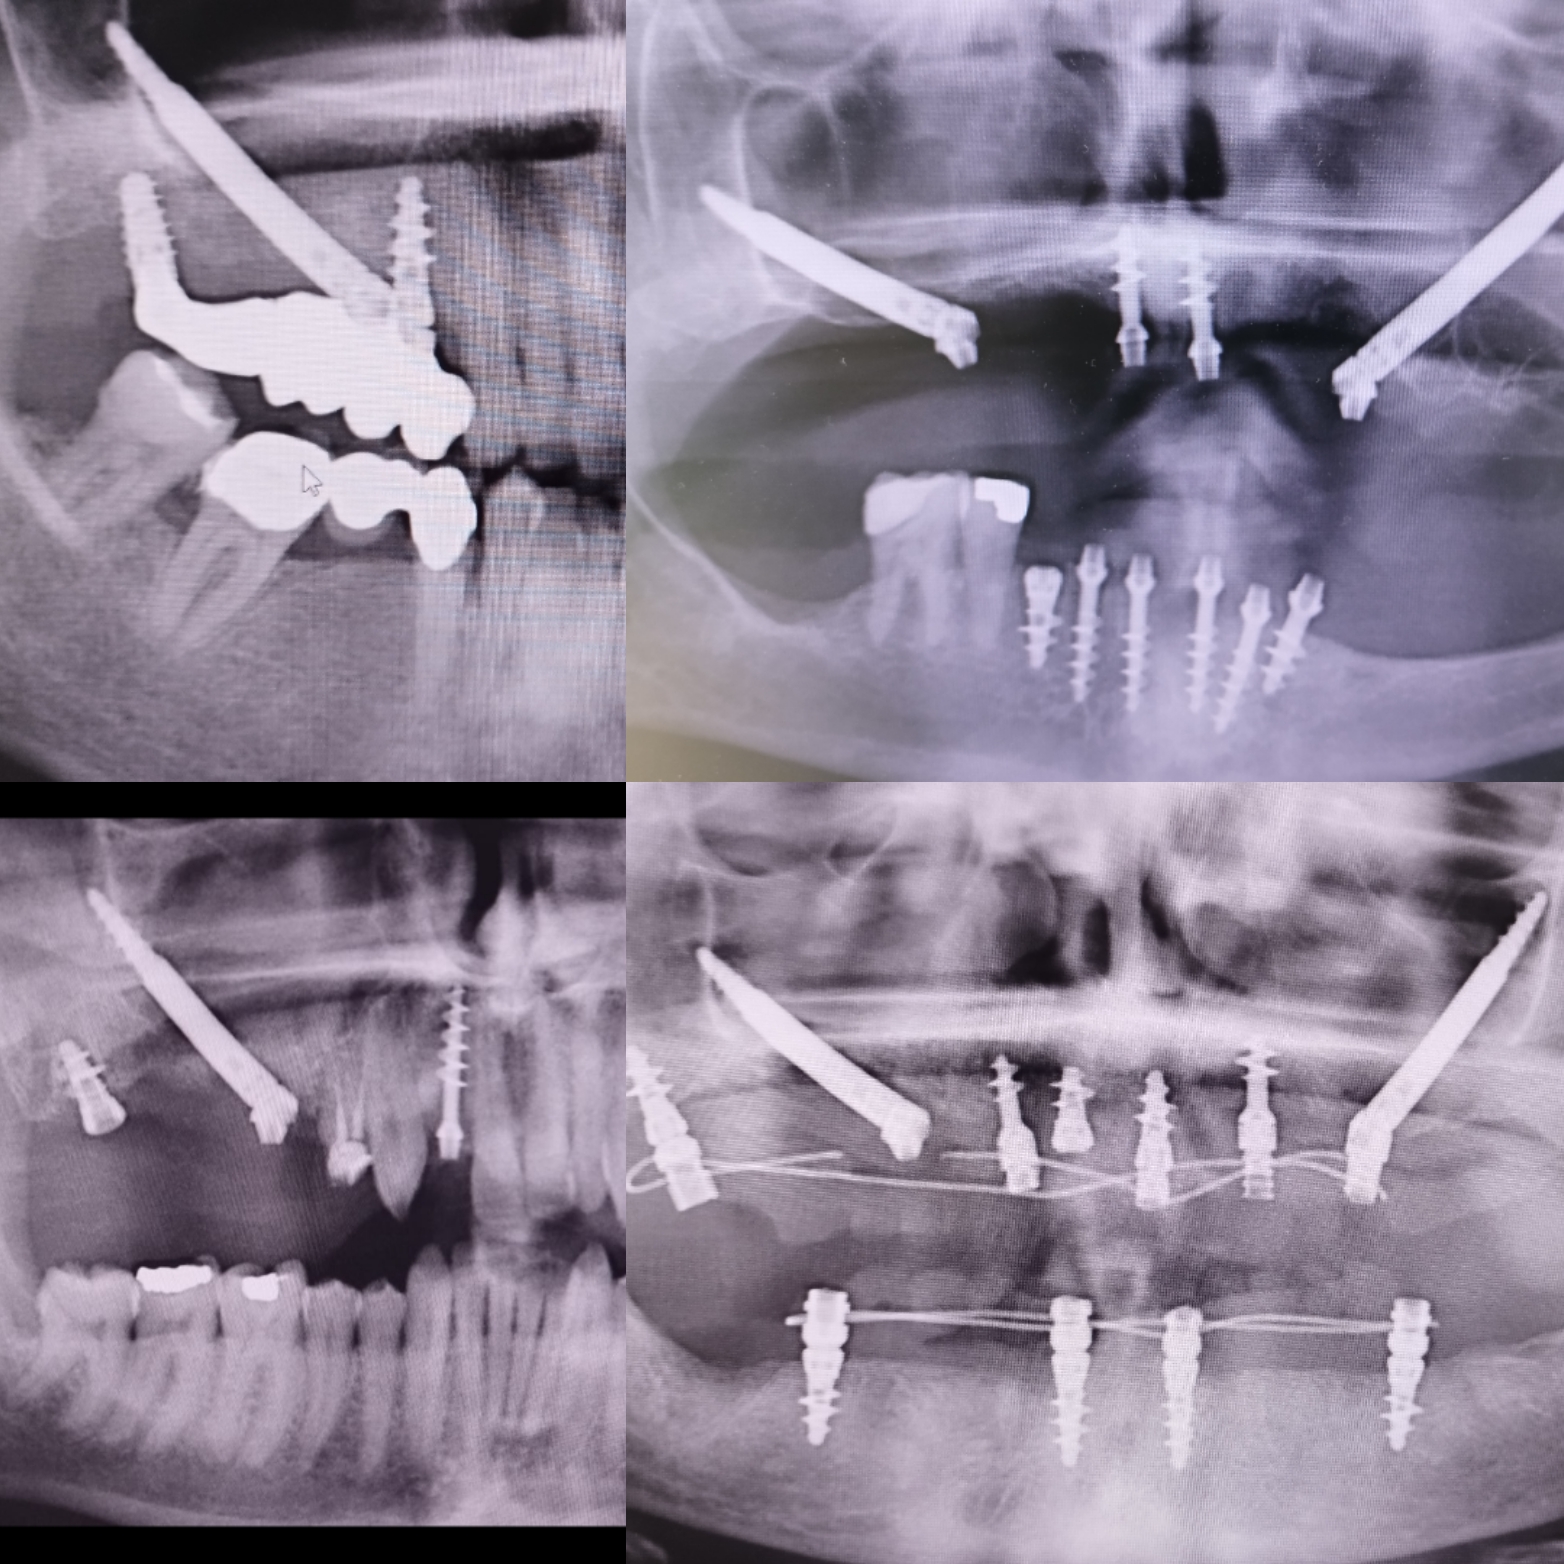

Buon giorno, offro consulenza per chirurgia orale, implantologia tradizionale, zigomatica e pterigoidea.